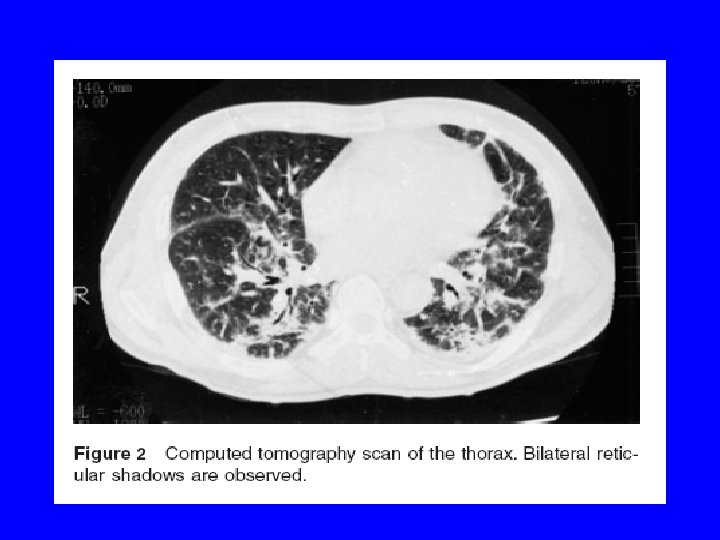

Case Report · 57 -year-old man was admitted to a hospital affiliated with dyspnea and dry cough lasting 2 weeks. · He had previously been diagnosed with rheumatoid arthritis, manifested by painful swelling of the joints 2 years prior to admission. · The patient was being treated with prednisone and gold. · Patient with diffuse pulmonary rheumatoid nodules and interstitial fibrosis throughout both lungs, is described. · The patient, with articular symptoms and seropositivity, exhibited a rapid clinical course and died of respiratory failure 3 months after the appearance of dyspnea.

· Chest radiography indicated interstitial pneumonitis with bilateral diffuse peripheral shadows. · At autopsy, numerous rheumatoid nodules and interstitial fibrosis had destroyed both lungs, such that no residual normal pulmonary tissue remained. · It is believed that this was an extremely rare case exhibiting large numbers of rheumatoid nodules throughout the lungs. · Findings with this patient indicate that, in patients with rheumatoid arthritis, clinical interstitial pneumonitis confirmed radiographically does not exclude the existence of rheumatoid lung nodules.